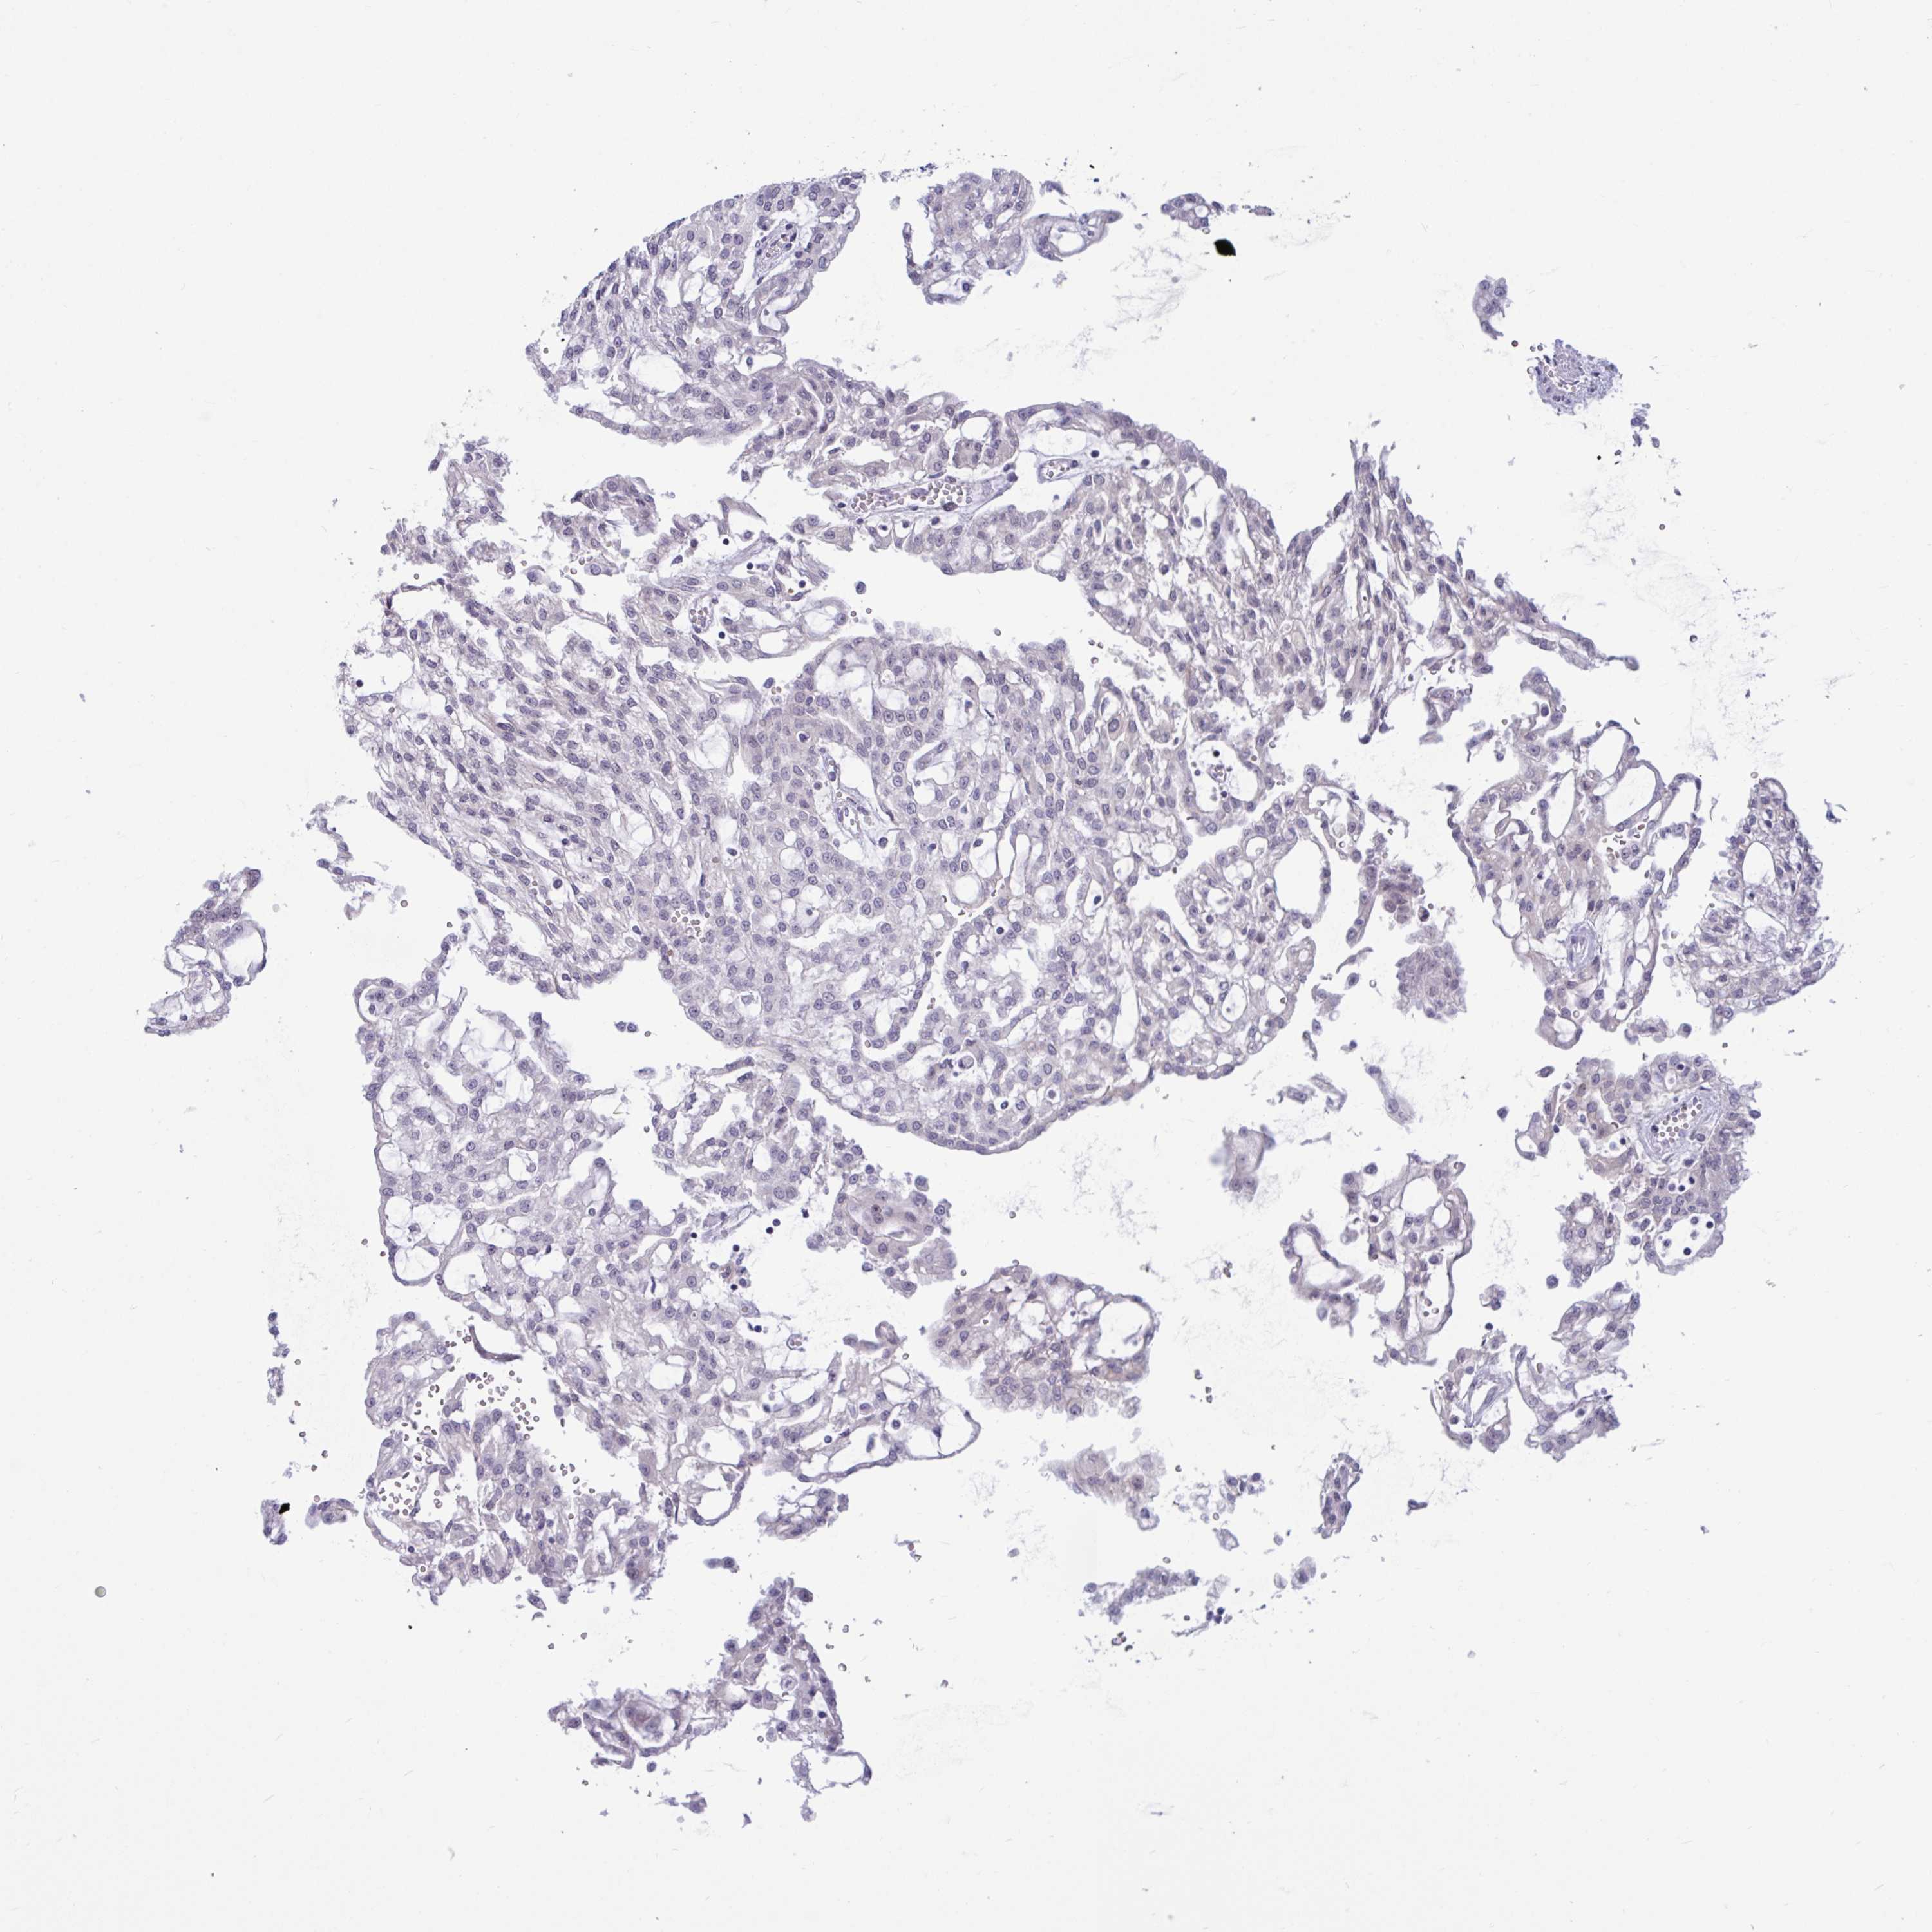

TCGA RNA samplesi

RNA-seq data is reported as average FPKM (number Fragments Per Kilobase of exon per Million reads), generated by the The Cancer Genome Atlas (TCGA) .

Normal distribution across the dataset is visualized with box plots, shown as median and 25th and 75th percentiles. Points are displayed as outliers if they are above or below 1.5 times the interquartile range. FPKM values of the individual samples are presented next to the box plot.

Average pTPM 0.1

Number of samples 521